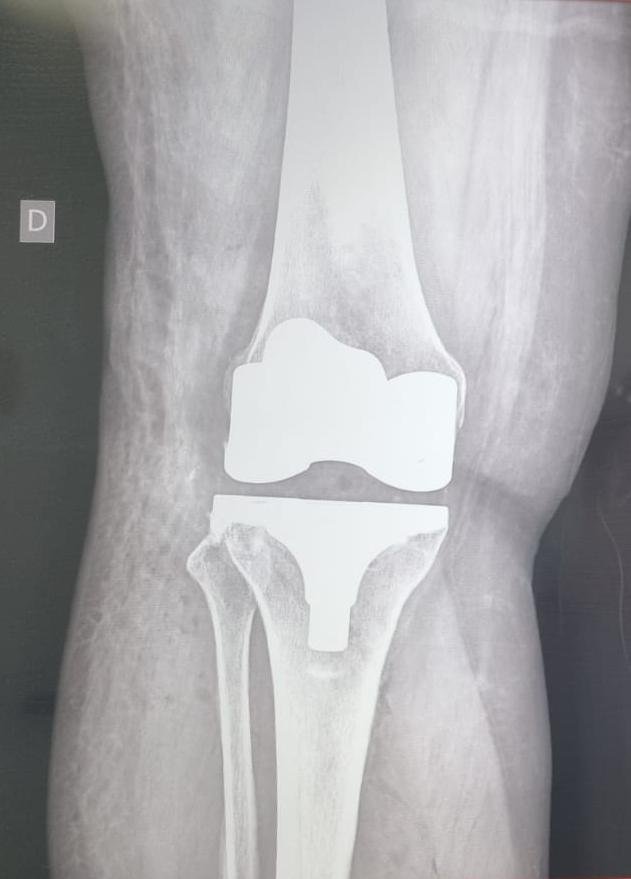

El Dr. José Luis Rodríguez García cuenta con el título de Especialista en Ortopedia y Traumatología.

Su compromiso con la salud y el rendimiento deportivo lo ha llevado a colaborar con la FIFA, aportando su experiencia médica en el cuidado, recuperación y prevención de lesiones de alto nivel competitivo.